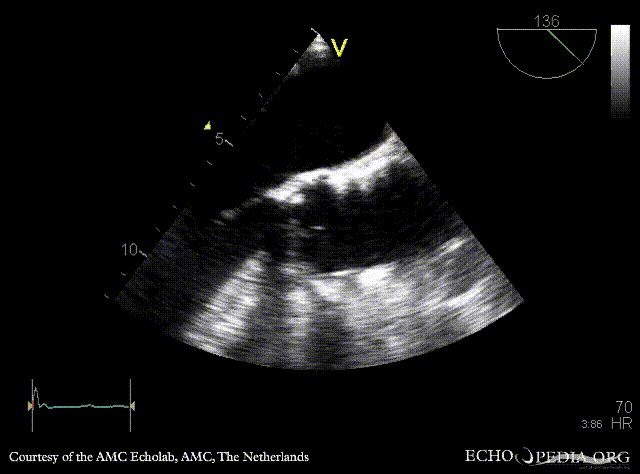

| TEE: dilated aorta | TEE: intramural hematoma of aorta |

| TEE: intramural hematoma of aorta | |